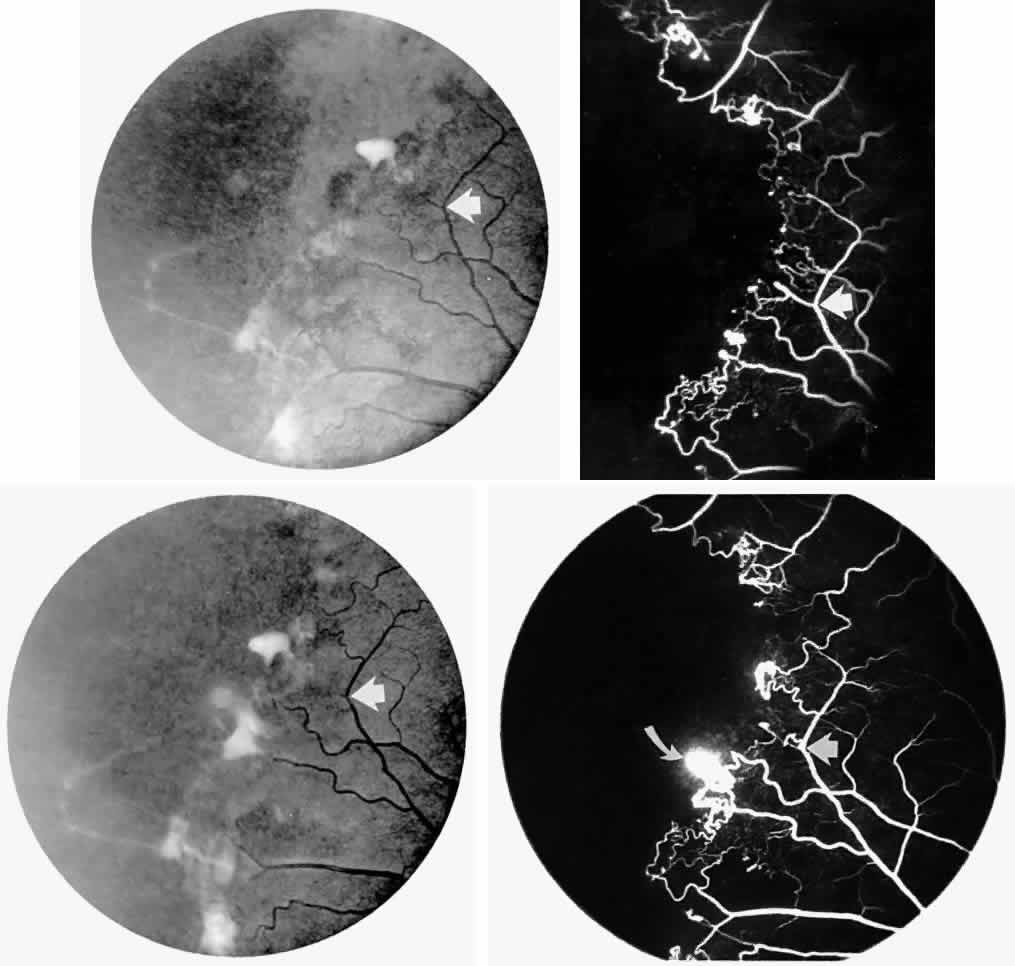

STAGE III: PRERETINAL NEOVASCULARIZATION (PROLIFERATIVE SICKLE RETINOPATHY). “Sea fan”-shaped neovascularization typically develops on the venular side of an arteriolar-venular anastomosis, mimicking the normal development of retinal capillaries (Fig. 24).125 A lowered oxygen tension and angiogenic factors released on the venular side may be the stimulus for neovascular growth.125,126 In most instances, the direction of growth is toward the ora serrata, from the perfused retina toward the nonperfused retina. Presumably, this represents an abortive attempt to revascularize the nonperfused retina, initiated by vasoproliferative factors.

The characteristic neovascular lesions of PSR are called sea fans because they resemble the marine invertebrate Gorgonia flabellum.70 They tend to occur more commonly in the temporal periphery, but they have been reported to occur in the temporal macula in the presence of extensive nonperfusion.130,133 Initially they grow on the surface of the retina, but they often become elevated into the vitreous and adhere to a partially detached posterior hyaloid.114 It may be difficult to visualize small sea fans ophthalmoscopically; however, fluorescein angiography clearly demonstrates leakage of dye into the vitreous (Fig. 25). The feeding arteriole is usually more tortuous than the draining venule (Fig. 26). Early on, the neovascular lesion is fed by a single arteriole and drained by a single venule, but with time, additional arterioles and venules become arborized within the lesion (Fig. 27).129 Growth of the sea fan often occurs circumferentially, rather than radiallyÜmh- 1Ý, toward the ora serrata. Progressive circumferential growth may lead to neovascular lesions extending around the entire periphery. As it matures, a white fibroglial mantle often covers the neovascular tissue (Color Plate 2B).

PSR is associated with the severe vision-threatening sequelae of sickle cell disease: vitreous hemorrhage (stage IV) and retinal detachment (stage V). These stages are believed to result from transudation of blood components into the vitreous through the incompetent neovascular tissue (Fig. 28). Vitreous fluorophotometry has quantified the leakage from the peripheral neovascularization.134 This leads to premature syneresis and collapse of the vitreous, inducing tractional forces on the retina that lead to vitreous hemorrhage, retinal tears, and tractional and rhegmatogenous retinal detachment. In rare cases, an exudative detachment may occur.

Spontaneous nonperfusion or autoinfarction, accompanied by regression of the neovascular lesion, occurs in 20% to 60% of eyes with PSR.135,136 The peak incidence of autoinfarction is 2 years after the development of PSR. It appears that autoinfarction occurs primarily as a result of (1) occlusion of the feeding arteriole due to traction on the neovascular lesion by contracting vitreous, or (2) occlusion by sickled RBCs. The latter probably is more common in homozygous sickle cell anemia, which is more commonly associated with autoinfarction and complete vascular occlusion.